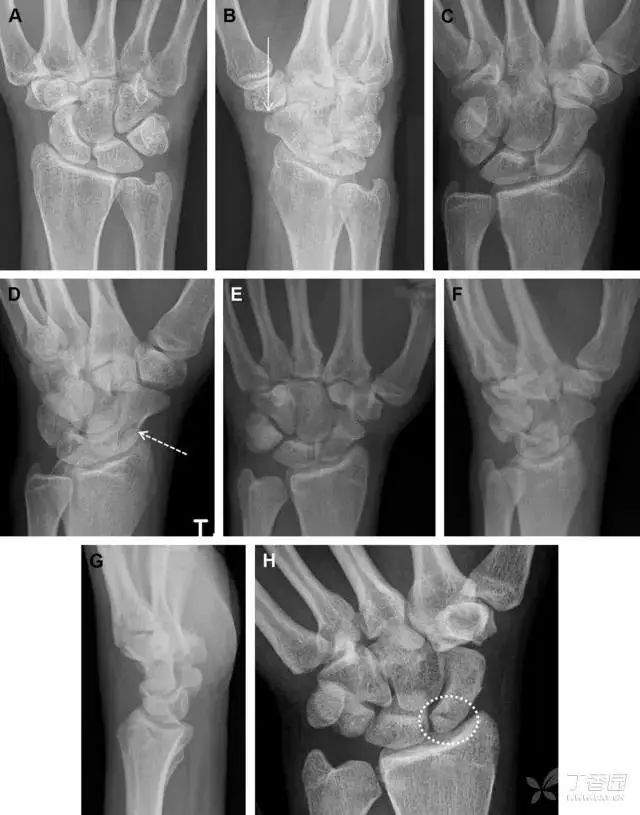

30桡骨远端骨折

常规进行前后位、侧位、斜位 X 线检查,对于大多数桡骨远端骨折来说不容易漏诊;但是对于无移位的骨折,特别是桡骨茎突骨折,容易漏诊。桡骨茎突骨折是一斜行的骨折,常累及关节面,常发生于轴向应力或直接打击。

图 1 57 岁女性,摔倒后手掌撑地,桡骨茎突压痛。(A~C)前后位、斜位、侧位片示软组织肿胀(*)和发丝样骨折(白色箭头);(D~F)2 周后,前后位、斜位、侧位片示骨折线显明,由于新骨痂沉积而呈现透亮线与硬化线并存;(G~I)另一患者,桡骨茎突骨折在前后位及侧位片上显示不明显,而在斜位片显示更清楚

31舟状骨骨折

舟状骨骨折 60%~70% 发生于腰部,15% 发生于近极, 10% 发生于远极, 8% 发生于远端关节面。除了常规的前后位、侧位、斜位片外,还需要拍专门的舟状骨位片(腕关节尺偏,以舟状骨为中心的腕关节前后位片),特别是鼻烟壶有压痛时。

图 2 舟状骨骨折 (A、B)第 1 例患者,舟状骨远极关节内骨折(白色箭头),斜位片显示较清楚(B);(C、D)第 2 例患者,舟状骨腰部骨折(虚线箭头),斜位片显示较清楚(D);(E~H)第 3 例患者,舟状骨近极骨折,常规 X 线片均未看到骨折,而在舟状骨位片上才能见到骨折(虚线圆)

32掌板骨折

掌板是掌指关节和指间关节关节囊掌侧的纤维结构,防止关节过伸。掌板的远端部是增厚的纤维软骨,附着于指骨掌侧基底部,而其两侧与侧副韧带的纤维融合。掌板骨折多发生于过伸损伤,为撕脱性骨折。

图 3 掌板骨折(A~C)小指前后位、斜位、侧位片,由于骨折的部位及特点,在前后位片上通常难以发现骨折;放大后的斜位(D)、侧位(E)可见一骨碎片(白色箭头)

33腕掌关节骨折脱位

腕掌关节骨折脱位为高能量损伤,常伴有神经损伤。腕掌关节组成骨多,侧位片上重叠遮挡多,骨折不易发现,容易漏诊。在前后位片上,关节面不平滑、关节间隙不对称、关节皮质破坏、关节面重叠常提示腕掌关节骨折脱位。特别是第 4、5 腕掌关节脱位,在前后位片上不容易发现;该损伤不稳定,也称为「变异型拳击手损伤/骨折」。

图 4 第 4、5 腕掌关节骨折脱位。(A)正常腕掌关节,关节面平衡起伏、平行;前后位(B)、斜位(C)、侧位(D),第 5 掌骨近端附近软组织肿胀(白色箭头),冠状面关节面重叠,背侧撞击剪切应力致钩状骨骨折(*),在前后位及斜位片上可见双密度影。第 4 掌骨底部可见微小骨折碎片(D,虚线箭头),第 4、5 掌骨掌侧成角。(E~G)变异型拳击手损伤:第 4、5 掌骨背侧脱位而未见骨折(E,虚线方框),钩状骨有骨折小碎片(F,短虚线箭头),第 4 掌骨基底部关节内骨折(G,长虚线箭头)

34钩状骨骨折

钩状骨骨折可发生于体部和钩部,钩部骨折更多见,可合并有第 4、5 腕掌关节脱位。受伤机制由直接暴力或腕横韧带撕脱伤所致。骨折征象包括钩部无显示、骨皮质边缘模糊、硬化或双密度影等。常规的正侧位常无法明确诊断,需要加拍腕管位,可清晰显示其钩部。

图 5 打高尔夫球后腕部急性疼痛。常规腕关节 X 线片正常(X)。腕管位片(B)隐约可见钩部横行骨折(虚线箭头),CT 检查(C、D)进一步明确了诊断

35三角骨骨折

三角骨骨折是除舟状骨骨折外腕关节常见的骨折之一。其背侧是背侧桡腕韧带的附着点,因此背侧骨折更常见。常规正侧位片基本可明确诊断。背侧骨折可在侧位片上看到一小骨块。

图 6 三角骨骨折。(A)前后位片骨折不明显,(B)仅在侧位片上见一小骨块(短箭头),伴有软组织肿胀(长箭头)。

36腕关节不稳定与脆弱区

月骨周围脱位和月骨周围骨折脱位常发生于摔倒后手掌撑地,由过伸、轴向暴力所致。所谓的「脆弱区」包括桡骨茎突、大多角骨、舟状骨、头状骨近端、钩状骨近端、三角骨的月骨缘、尺骨茎突。

图 7 经舟状骨骨折月骨周围脱位(腕关节前后位、斜位、侧位)。(A,B)前后位、斜位示月骨腰部骨折(黑箭头),第 1、2 腕弧中断,舟状骨近极(*)仍在原位,而远极(虚线)背侧脱位